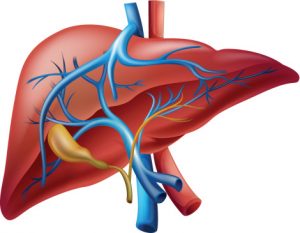

Why you can’t take your liver for granted

We all want to drink clean water, and so we’ll head out and buy special filters to help provide that for us. We fill up the jug and the water slowly trickles through the filter making it as clean and pure as it can. But after a while the filter may get clogged and diminish in efficiency, and so we head out and buy new filters and the cycle continues.

You may be asking why we’re discussing water filters, but when you think of a water filter it should remind you of a very important organ in your body. We’re talking about your liver.

Your liver and a water filter have much in common. The difference, though, is when your liver becomes damaged, weighed down and inflamed, you can’t just toss it out and get a new one. It’s the only organ in the body that can regenerate itself, so it has to work through all the damage and heal itself – no easy task if your lifestyle doesn’t support a healthy liver. With this in mind, liver protection is essential.